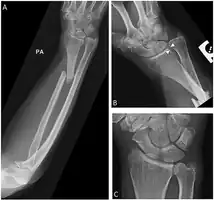

Galeazzi fracture

| Galeazzi fracture-dislocation | |

| Galeazzi fracture. Arrow points at the dislocated ulnar head | |

The Galeazzi fracture is a fracture of the distal third of the radius with dislocation of the distal radioulnar joint. It classically involves an isolated fracture of the junction of the distal third and middle third of the radius with associated subluxation or dislocation of the distal radio-ulnar joint; the injury disrupts the forearm axis joint.[1]

The dislocation of ulnar head in Galeazzi fracture dislocation may be dorsal (commoner) or volar (rare) depending on the mechanism of injury. If the fall is on the outstretched hand with forearm in pronation, the dislocation is dorsal, and if forearm is in supination at the time of injury, the dislocation is volar.[2]

Galeazzi fractures are best treated with open reduction of the radius and the distal radio-ulnar joint.[3] It has been called the "fracture of necessity," because it necessitates open surgical treatment in the adult.[4] Nonsurgical treatment results in persistent or recurrent dislocations of the distal ulna.[1] However, in skeletally immature patients such as children, the fracture is typically treated with closed reduction.[1]

Images

-

Galeazzi fracture after surgical fixation